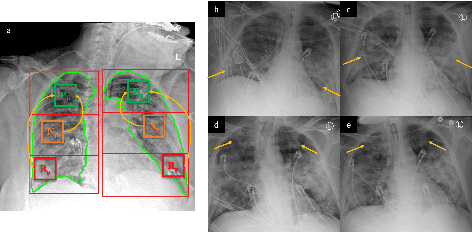

COVID-19 image analysis has mostly focused on diagnostic tasks using single timepoint scans acquired upon disease presentation or admission. We present a deep learning-based approach to predict lung infiltrate progression from serial chest radiographs (CXRs) of COVID-19 patients. Our method first utilizes convolutional neural networks (CNNs) for feature extraction from patches within the concerned lung zone, and also from neighboring and remote boundary regions. The framework further incorporates a multi-scale Gated Recurrent Unit (GRU) with a correlation module for effective predictions. The GRU accepts CNN feature vectors from three different areas as input and generates a fused representation. The correlation module attempts to minimize the correlation loss between hidden representations of concerned and neighboring area feature vectors, while maximizing the loss between the same from concerned and remote regions. Further, we employ an attention module over the output hidden states of each encoder timepoint to generate a context vector. This vector is used as an input to a decoder module to predict patch severity grades at a future timepoint. Finally, we ensemble the patch classification scores to calculate patient-wise grades. Specifically, our framework predicts zone-wise disease severity for a patient on a given day by learning representations from the previous temporal CXRs. Our novel multi-institutional dataset comprises sequential CXR scans from N=93 patients. Our approach outperforms transfer learning and radiomic feature-based baseline approaches on this dataset.